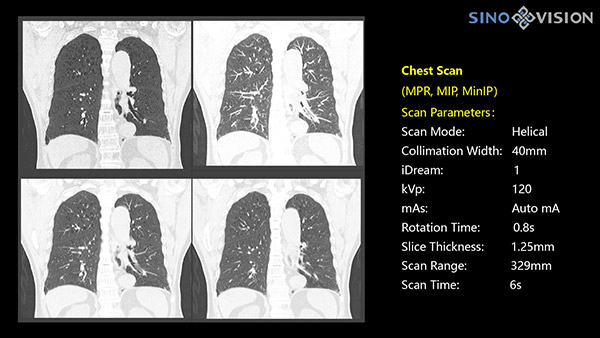

Инновационный 128-срезовый компьютерный томограф SinoVision InsitumCT 568 – это сочетание высокой скорости работы, низкой дозы и максимума возможностей для подавляющего большинства клинических случаев, как в рутинных, так и в углубленных специализированных исследованиях, в том числе педиатрические и кардиологические исследования при сверхнизких дозах.

Полнофункциональный 128-резовый компьютерный томограф InsitumCT 568 - это лучшее в новом поколении широкодиапазонных томографов с 128 срезами и большой диафрагмой. Этот КТ-сканер с большой апертурой обеспечивает 128 срезов КТ с диафрагмой 76 см, улучшает разрешение изображения до 21Lp/cm, помогает точно диагностировать и лечить заболевания, а также значительно улучшает клинические характеристики и расширяемость оборудования. Позволяет реализовать визуализацию в высоком разрешении и в малых дозах лучевой нагрузки.

Полнофункциональная платформа клинической диагностики может точно определять местонахождение и диагностировать общие повреждения качественно и количественно, а также достигать полнофункциональных клинических показателей, включая обширные кардиологические исследования со сверхнизкими дозами лучевой нагрузки.